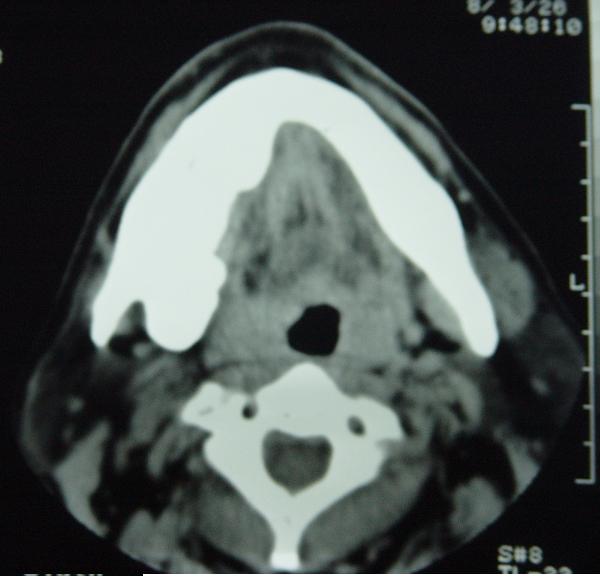

标题: CT12465:下颌骨肿瘤,请会诊 [打印本页]

标题: CT12465:下颌骨肿瘤,请会诊

发现下颌骨肿瘤近30年.逐渐增大.

考虑右侧下颌骨水平部及升部骨纤维异常增殖症可能性大。